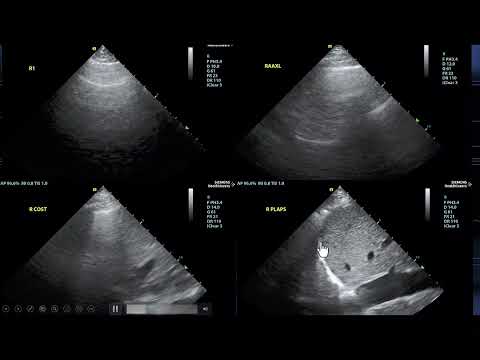

Advanced Critical Care Echocardiography - Complete Exam

Advanced Critical Care Echocardiography - Complete Exam

Jose Diaz-Gomez | Critical Care Echocardiography